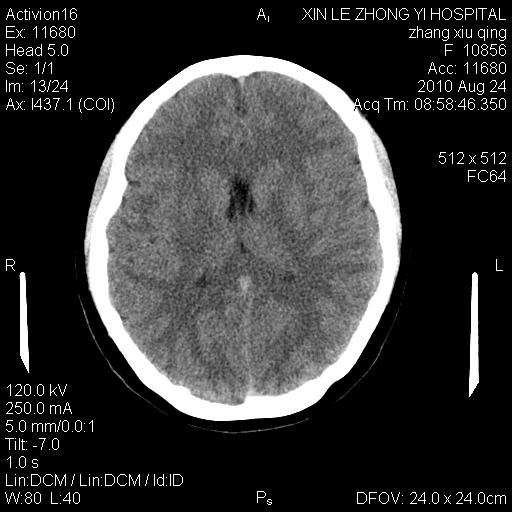

标题: CT28569:看看鞍上池正常吗 [打印本页]

标题: CT28569:看看鞍上池正常吗

女 24 偶有头晕

怎么这么多伪影?我感觉没什么特别异常哦,是不是伪影所至呀

未见明显异常,必要时可作mri